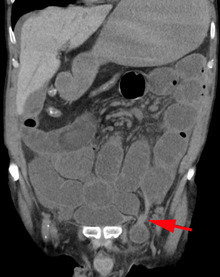

An inguinal hernia which contains part of the bladder. Bladder cancer also present.

When assessed by ultrasound or cross sectional imaging with CT or MRI, the major differential in diagnosing indirect inguinal hernias is differentiation from spermatic cord lipomas, as both can contain only fat and extend along the inguinal canal into the scrotum.[22]

On axial CT, lipomas originate posterolateral to the cord, and are located inside the cremaster muscle, while inguinal hernias lie anteromedial to the cord and are not intramuscular. Large lipomas may appear nearly indistinguishable as the fat engulfs anatomic boundaries, but they do not change position with coughing or straining.[22]